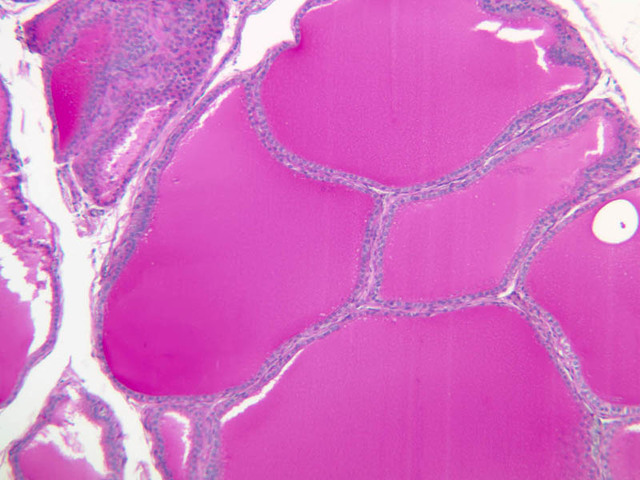

The thyroid gland (slide B-51, lead hematoxylin [10x, 20x, 40x, 40x]; B-52, H&E [10x-labeled, 20x, 40x-labeled, 40x]; B-53, PAS [2.5x, 10x, 20x, 40x]) consists of many closely packed, roughly spherical structures known as follicles, which are enclosed in a thick connective tissue capsule. Connective tissue septa extend from the capsule into the substance of the gland, carrying numerous blood vessels. Follicular cells are arranged as shells of simple cuboidal epithelium surrounding a gelatinous mass known as colloid. Look for a ring of epithelial cells around the homogeneous, pink-staining colloid. The cytoplasm of the follicular cells (principal cells) is faintly basophilic. The follicular cells secrete thyroglobulin, a glycoprotein, which is stored extracellularly in the colloid. In response to TSH, the follicular cells endocytose the colloid and hydrolyze it to form thyroxine. You can see where colloid has been resorbed because this process leaves small holes in the colloid adjacent to the follicular cells. These holes are known as resorption lacunae (B-52 [10x, 20x, 40xlabeled]). Very active follicles may exhibit a columnar epithelium and increased numbers of resorption lacunae. Between follicles, the stroma of the thyroid gland consists of a thin layer of connective tissue and a rich capillary network. Parafollicular cells (light cells or C cells) are located in the connective tissue between follicles or adjacent to follicular cells within follicles. When they lie within the follicular wall, the parafollicular cells do not reach the lumen. Parafollicular cells are slightly larger than the follicular cells and, in H & E preparations, have a more lightly stained cytoplasm (B-52, H&E [10x, 20x, 40x-labeled] [10x-labeled, 20x, 40x-labeled] [10x, 20x, 40x] [10x, 20x, 40x]; B-53, PAS [10x, 20x, 40x]). Parafollicular cells are readily identifiable in slide B-51 (stained with lead hematoxylin), where they appear as purplish-black structures in which the nuclei are difficult to discern (B-51 [10x, 20x, 40x-labeled]). These cells secrete calcitonin, which lowers serum calcium levels by inhibiting bone resorption and accelerating osteoid calcification.